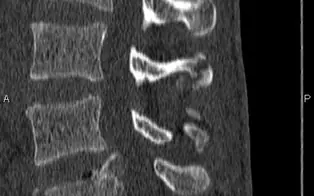

Rachis dorso-lombaire